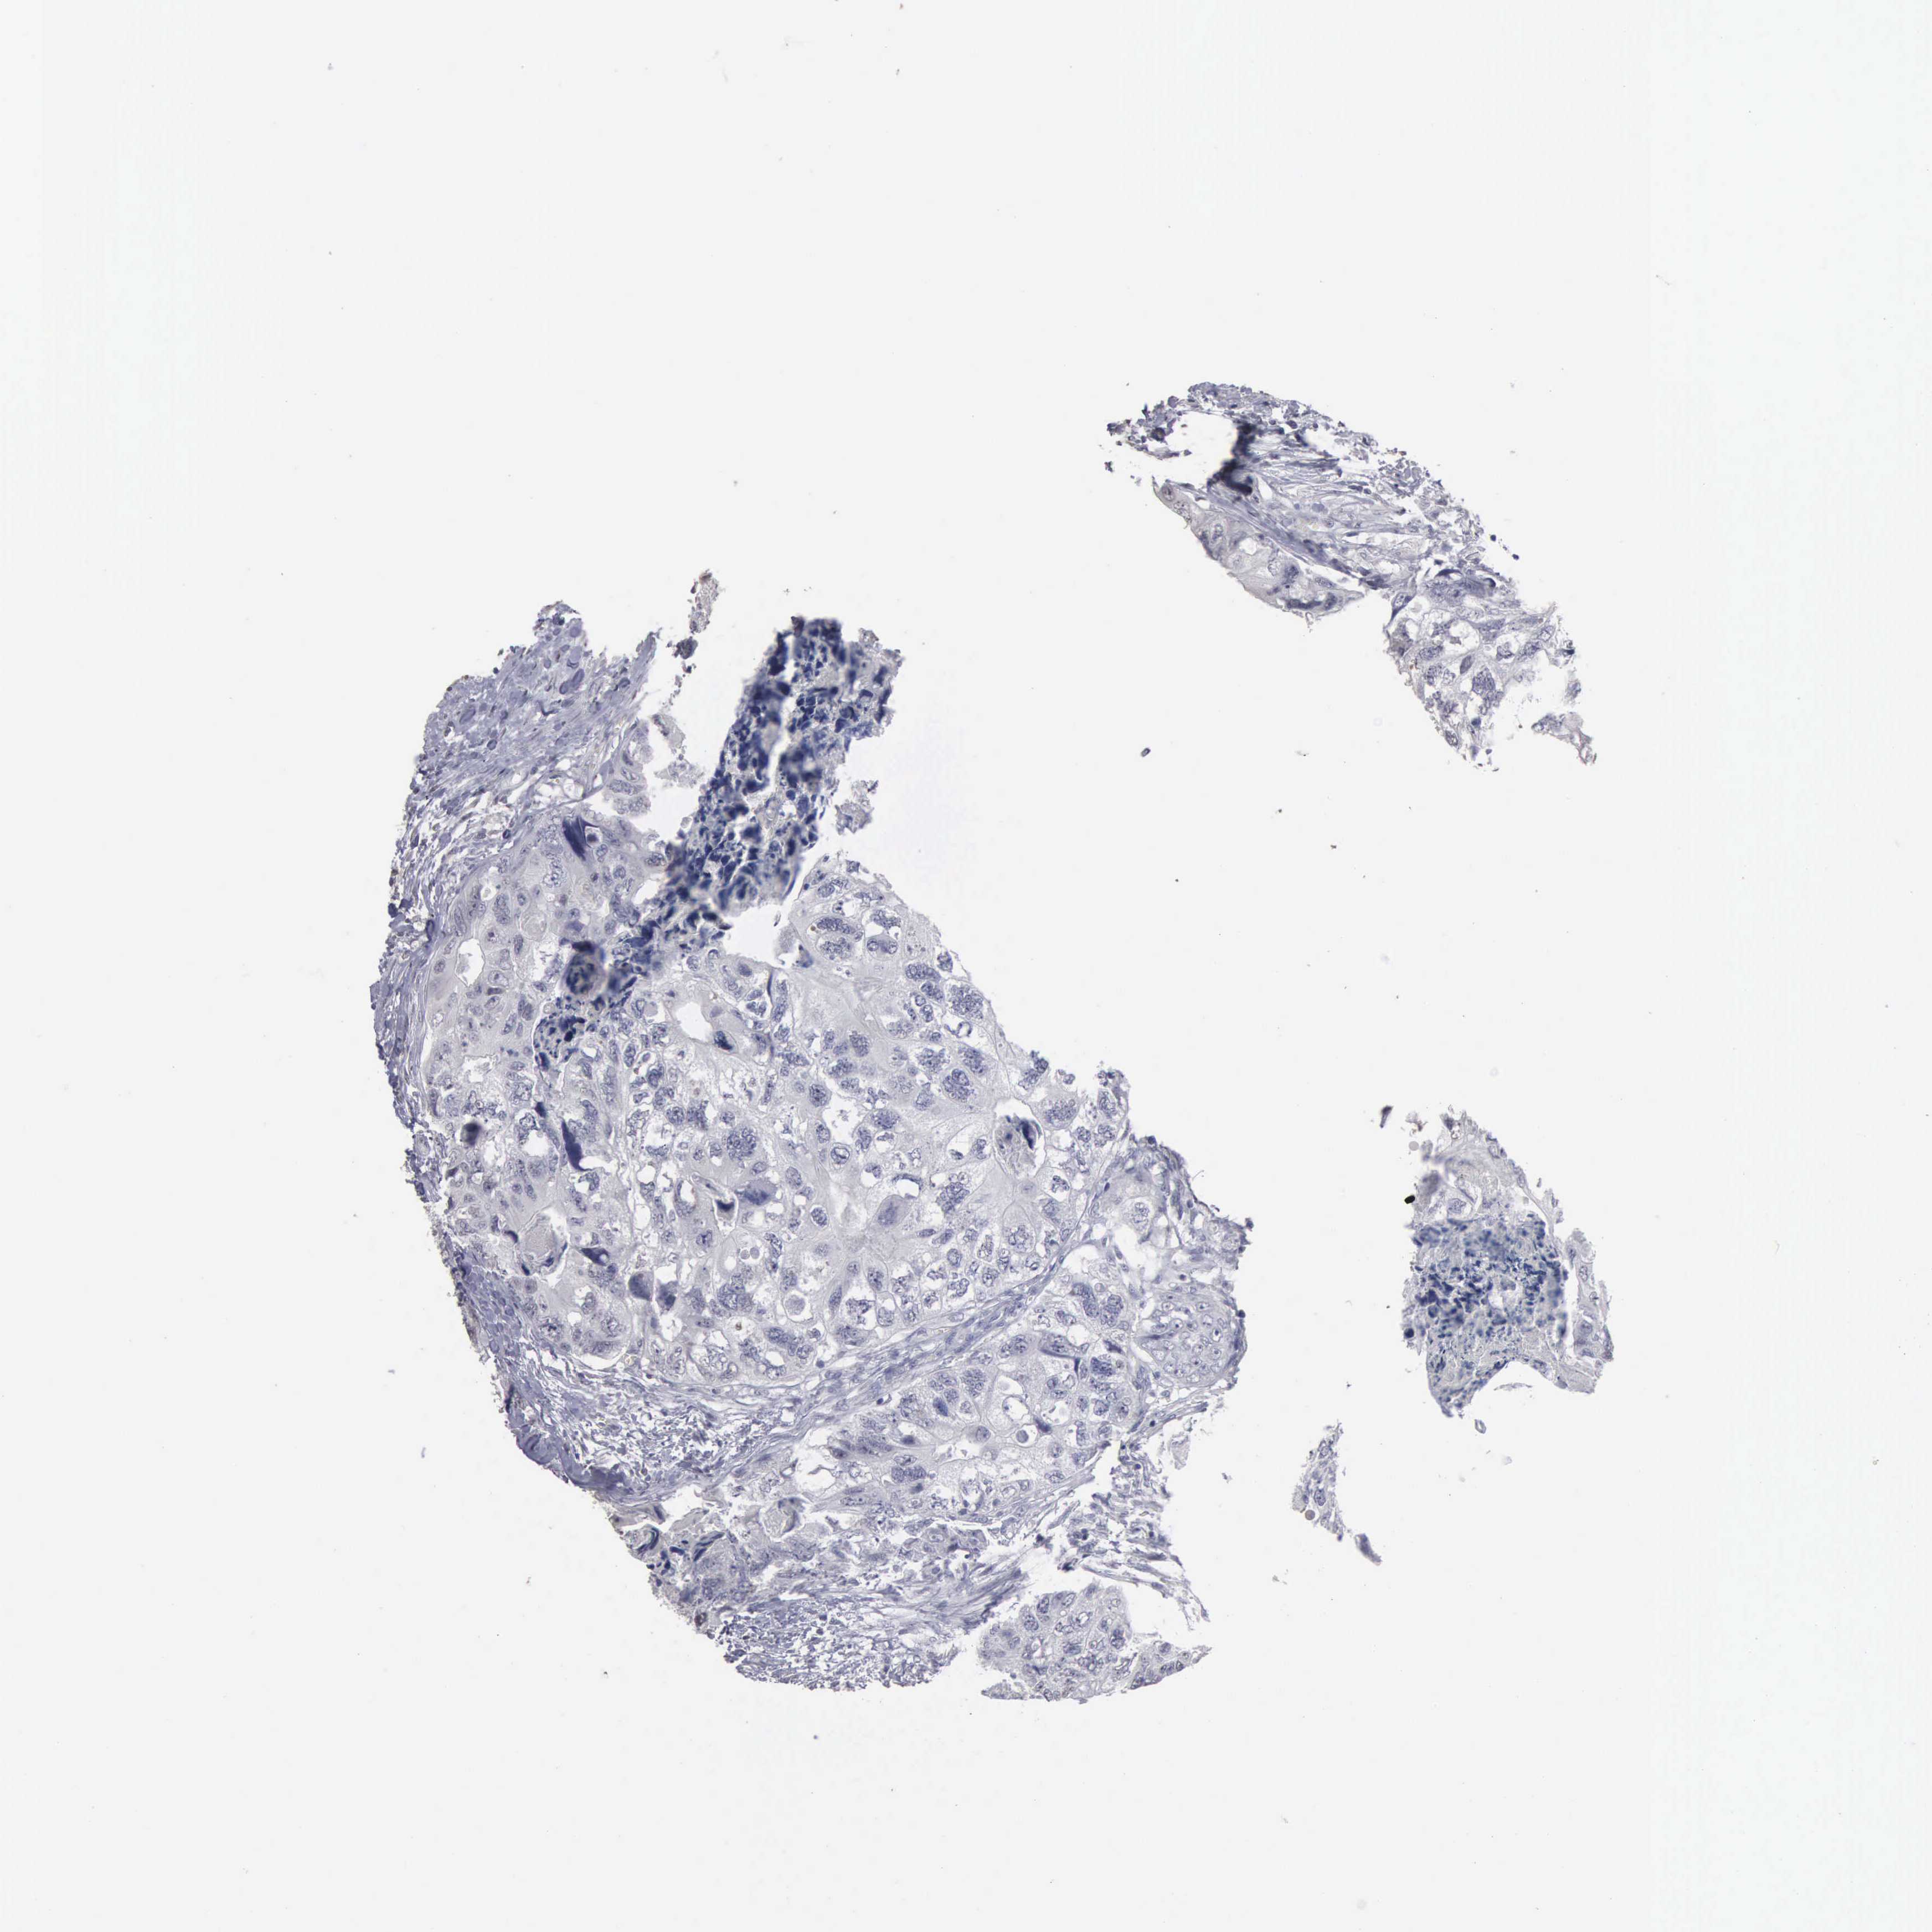

CANCER COLORECTAL CANCER Show tissue menu

ANTIBODIES

AND

VALIDATION

Colorectal cancer

Human cancer

Colon adenocarcinoma